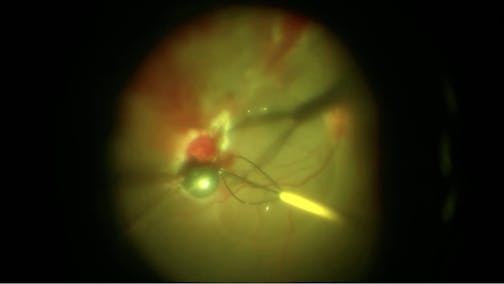

Acute Retinal Necrosis

J. Fernando Arevalo, MD, PhD